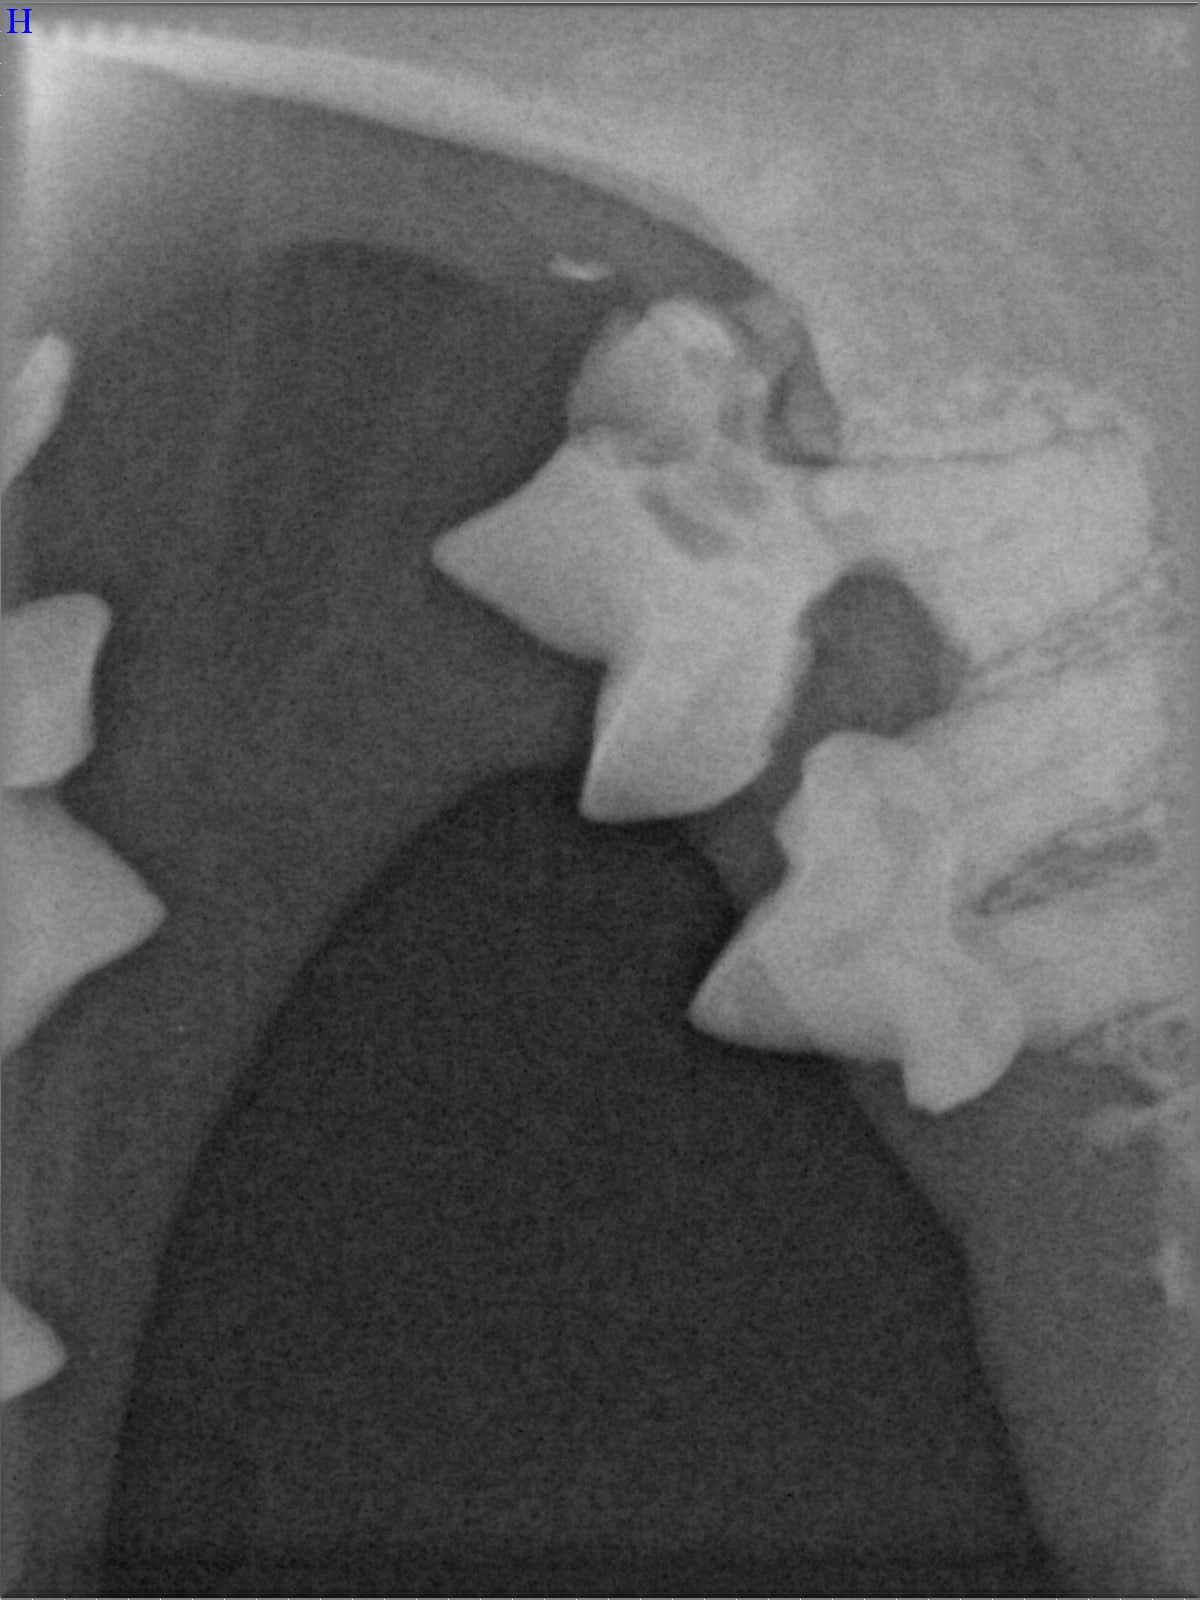

Ein entscheidender Baustein der FORL-Diagnostik ist das dentale Röntgen. Viele Läsionen sind von außen nicht sichtbar und lassen sich ausschließlich mithilfe moderner Röntgentechnik erkennen. In der Hamburger Praxis kommt digitales Dentalröntgen zum Einsatz, das detailreiche Aufnahmen bei geringer Strahlenbelastung ermöglicht. So kann FORL bereits in frühen Stadien diagnostiziert werden.

Das sehen Sie von außen – so sieht es auf den Röntgenbildern aus.

FORL Katze Röntgenbild

Röntgenbilder